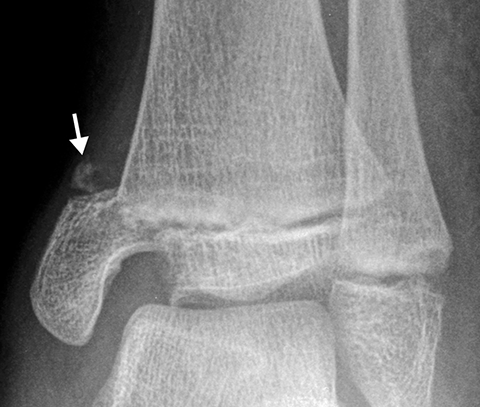

Salter-Harris fractures[2 of 3]